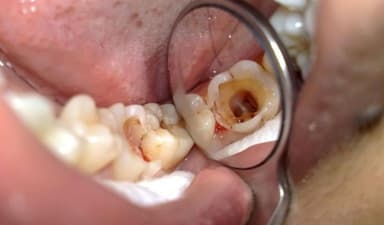

– Các chấm đen xuất hiện có thể nhìn thấy bằng mắt thường. Chấm đen dần dần lan ra, hình thành các lỗ sâu răng lớn.

– Bề mặt răng có màu nâu, ngả màu do tình trạng sâu răng đã lan đến tủy và làm tổn thương tủy răng.

Khi bị sâu, răng số 6 thường xuất hiện các chấm đen, hốc sâu răng trên bề mặt